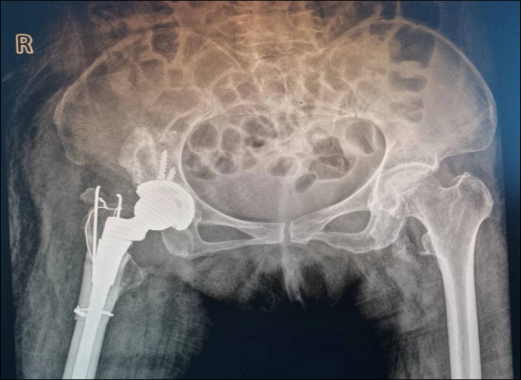

吴战坡 骨科执行主任,主任医师,骨科博士,副教授,硕士研究生导师。 江苏省中西医结合骨伤委员会委员,南京市医学会骨科分会委员,中华医学会河北省分会足踝外科专业学组委员,河北省老年医学会骨与关节损伤专业委员会常委。河北省中西医结合学会骨伤科委员会委员。南京市中医药学会外治委员会副主任委员。发表SCI论文6篇,中华医学会论文5篇,中文核心20余篇。参与编写专著3部,任编委。获国家发明专利一项。参与省市级多项科研课题,2017年获省级科技进步二等奖一项。 擅长诊断处理骨科各部位创伤及保肢治疗,骨盆骨折及四肢关节内骨折、髋、膝关节置换及翻修手术,膝髋关节病的阶梯化治疗及关节镜手术、脊柱骨折及颈腰椎间盘突出症手术治疗、各种儿童骨折及矫形手术等。指导下级医师及研究生的临床及科研工作。 高级专家门诊时间:每周三。 在南京市溧水区人民医院骨科,一线医护工作中,每天都发生着许许多多的动人故事:一次成功的抢救,一次艰苦的手术,乃至一句叮咛,一个微笑,落在患者眼里,都能化作无限的感动。溧医骨科人始终肩负着“病人至上、服务第一”的使命,以医者仁心谱写一曲曲生命赞歌。 一路风尘一路歌,兢兢业业践初心。翻开骨科执行主任吴战坡的履历,一位医者刻苦学习、积极钻研业务的生动形象呼之欲出:吴战坡主任通过不断刻苦学习与进步,在全军最高学府解放军医学院(301医院)获骨科硕士学位,后师从中国工程院院士张英泽教授,获得骨科博士学位。主任医师,副教授,硕士生导师。2018年通过人才引进来到南京市溧水区人民医院。擅长处理骨科各部位创伤及保肢治疗,骨盆骨折及四肢关节内骨折、髋、膝关节置换及翻修手术,膝髋关节病的阶梯化治疗及关节镜手术、脊柱骨折及颈腰椎间盘突出症手术治疗、各种儿童骨折及矫形手术等。工作之余,他勤奋好学,精益求精,通过微信课堂、手术视频、英文杂志等各种途径了解最新的医学动态,每年均多次参加省内外各种学术会议,聆听著名专家学者的学术讲座,开阔视野,扩大知识面,与时俱进。目前担任的学术任职有:江苏省中西医结合骨伤委员会委员;南京市医学会骨科分会委员,中华医学会河北省分会足踝外科专业学组委员;河北省老年医学会骨与关节损伤专业委员会常委;河北省中西医结合学会骨伤科委员会委员;南京市中医药学会外治委员会副主任委员。吴战坡主任不但医术高超,在学术方面也是硕果累累,已发表SCI论文6篇;中华医学会论文5篇;中文核心20余篇;参与编写医学专业著作3部;获国家发明专利一项;参与省市级多项科研课题,2017年获省级科技进步二等奖一项。 案例一 2021年,女性患者刘某,68岁,因先天性髋关节脱位,肢体短缩,严重影响生活质量,辗转多地治疗后无效,多方打听得知溧水区人民医院骨科吴战坡主任是关节疾病的诊疗专家,遂慕名而来。吴战坡主任格外重视,对其进行了仔细专科查体及影像学评估,诊断为右侧先天性髋关节脱位,关节强直,此类手术难度大,风险高,以往此类患者须请上级医院专家会诊或者转院上级医院治疗。吴战坡主任经过详细的术前讨论及准备后,成功开展了溧水区内首例高脱位髋关节置换手术,此例手术的成功开展,填补了我院骨科技术在该领域的空白,标志着我院关节骨科在关节疾病治疗上的又一进步,在溧水区打响了自家门口就有关节专家的招牌。 近几年,关节外科在吴战坡主任及其团队的不断努力下,成功开展了数十例复杂的人工全髋关节置换手术,这其中包括强直髋关节和髋关节翻修等等。在过去,这类患者往往需要乘坐数小时的车程去南京上级医院就诊,而现在,名医在溧水,让老百姓花更少的时间,在家门口就能享受到专家看病。这类复杂手术的成功开展,标志着我院关节骨科的又上一台阶。 案例二 患者邰某,男性,65岁,数年前因外伤致左胫骨平台骨折,未经正规治疗,遗留膝关节外翻位畸形,后畸形逐渐加重,疼痛明显,无法行走,经人介绍来吴战坡主任门诊就医,膝关节外翻治疗难度较内翻膝困难,而严重外翻膝的治疗更加复杂,严重外翻膝由于后侧、外侧组织挛缩严重,内侧入路不易松解,且外侧结构多,稳定性远低于内侧,关节外科医生很少选择此入路,操作不当会造成术中操作困难,增加创伤,影响术后功能。患者邰某膝关节外翻是由于骨折后畸形愈合所致,周围结构失去正常解剖关系,大量骨痂形成,后外侧软组织挛缩严重,内侧松弛,髌骨脱位,如何有效治疗是骨科关节外科医生面临的一项挑战。吴战坡主任不畏困难,带领团队术前进行详细的讨论和准备,顺利完成了膝关节的置换手术。术后患者恢复状况良好,对治疗效果非常满意。 医生常常需要了解许多领域的知识,我们常常说医学的对象是人,人不仅是自然个体而且是社会成员,除了医学知识和技术,医生还需要了解社会科学知识,从社会的背景下为患者考量治疗的方案和目标,才能真正将医生治疗的目的与患者治疗的期望结合起来。溧水区人民医院骨科作为南京市重点专科,吴战坡教授带领团队在关节置换和骨盆疾病的治疗的主攻方向上积极开展新技术、新项目,开展的髋、膝关节置换治疗水平处于本地区领先地位,优质的医疗技术服务辐射溧水周边高淳、江宁地区,甚至造福了许多省外病人。 在专业的领域做到极致,探索疾病致病机理最艰深神秘的领域,让更多患者接受更高质量的治疗,是吴战坡作为医生的执着和坚守。医者仁心,对于希望患者不再为疾病所苦的强烈期望和精益求精的职业精神,引领着无数医生不断深化对于疾病的研究和认识,在医学的领域勇攀高峰,吴战坡正是这一信念的坚定践行者。 以爱为医 奔赴山海